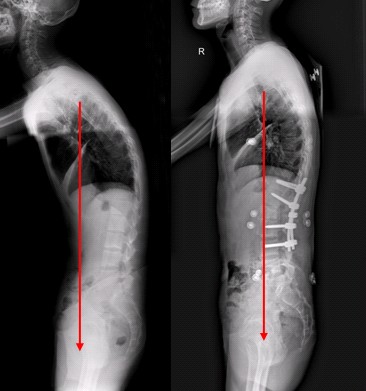

QZ16030094 姓名:陈先生 性别:男 年龄:32岁

- 病情

AS ①晚期 ②重度 病史:5年+

- 治疗

治疗后骶髂关节疼痛消失,腰椎前屈、背伸侧弯活动自如,膝关节无压痛感,复查血沉、C反应蛋白、等各项检查均已达到临床康复的标准。